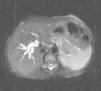

Se presenta el caso de una niña de 3 años remitida por acolia, coluria y astenia de 10 días de evolución, que asociaba dolor abdominal difuso no irradiado, exacerbado con la ingesta y prurito generalizado de 3 días de evolución. No había antecedentes personales ni familiares de interés. Presentaba ictericia mucocutánea, lesiones excoriativas en extremidades compatibles con rascado y abdominalgia a la palpación en la región periumbilical. Se evidenció hipertransaminasemia (GOT 67 U/l, GPT 86 U/l, GGT 124 U/l, ALP 958 U/l); hiperbilirrubinemia directa (total: 3,6mg/dl, conjugada 2,94mg/dl) y elevación importante de enzimas pancreáticas (lipasa 2.512 U/l y amilasa 1.817 U/ml). La ecografía abdominal mostró dilatación segmentaria de conductos hepáticos con aumento del tamaño vesicular sin presencia de cálculos, no identificándose la entrada del colédoco en la papila. Los estudios infecciosos (cultivos y serologías) resultaron negativos. La colangio-RM visualizó la presencia de 2 cálculos en colédoco distal y barro biliar con dilatación de la vía biliar intra y extrahepática (calibre máximo 9mm) y la presencia de un conducto cístico dilatado, con una longitud superior a la normal (3,5cm), junto a un canal biliopancreático común (figs. 1 y 2). No se observaron otras anomalías a nivel pancreático. Se realizó valoración quirúrgica y se completó el estudio con CPRE, diagnosticándose de quiste de colédoco forma frustra con dilatación intrahepática asociada. Se realizó resección de vía biliar con reconstrucción bilioentérica en Y de Roux. Ha sido reevaluada posteriormente, mostrando buena evolución, estando asintomática y sin alteraciones analíticas.

La clasificación de los quistes de colédoco más aceptada es la realizada por Todani en 1978, que incluye 5 tipos2. Los quistes tipo i, con dilatación quística o fusiforme del colédoco o del conducto hepático común, son los más frecuentes (75-80%)1. En las últimas décadas, gracias al uso extendido de la colangio-RM, surgen nuevas clasificaciones. Se habla de forma frustra de quiste de colédoco ante la presencia de una dilatación leve (< 10mm) del colédoco asociada a una mala unión biliopancreática5,6. Nuestro caso presenta estos hallazgos junto con una dilatación de la vía biliar intrahepática, lo que puede ocurrir hasta en un 60% de los casos. Además, se encuentran litiasis o barro biliar intrahepático casi en 10% de las ocasiones5.